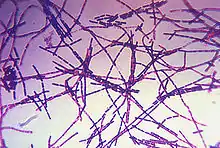

Bacillus anthracis is a rod-shaped, Gram-positive, facultative anaerobic bacterium about 1 by 9 μm in size.[2] It was shown to cause disease by Robert Koch in 1876 when he took a blood sample from an infected cow, isolated the bacteria, and put them into a mouse.[23] The bacterium normally rests in spore form in the soil, and can survive for decades in this state. Herbivores are often infected while grazing, especially when eating rough, irritant, or spiky vegetation; the vegetation has been hypothesized to cause wounds within the GI tract, permitting entry of the bacterial spores into the tissues, though this has not been proven. Once ingested or placed in an open wound, the bacteria begin multiplying inside the animal or human and typically kill the host within a few days or weeks. The spores germinate at the site of entry into the tissues and then spread by the circulation to the lymphatics, where the bacteria multiply.

Bacillus anthracis

Bacillus anthracis Color-enhanced scanning electron micrograph shows splenic tissue from a monkey with inhalational anthrax; featured are rod-shaped bacilli (yellow) and an erythrocyte (red)

Color-enhanced scanning electron micrograph shows splenic tissue from a monkey with inhalational anthrax; featured are rod-shaped bacilli (yellow) and an erythrocyte (red) Gram-positive anthrax bacteria (purple rods) in cerebrospinal fluid: If present, a Gram-negative bacterial species would appear pink. (The other cells are white blood cells.)

Gram-positive anthrax bacteria (purple rods) in cerebrospinal fluid: If present, a Gram-negative bacterial species would appear pink. (The other cells are white blood cells.)

Various techniques may be used for the direct identification of B. anthracis in clinical material. Firstly, specimens may be Gram stained. Bacillus spp. are quite large in size (3 to 4 μm long), they may grow in long chains, and they stain Gram-positive. To confirm the organism is B. anthracis, rapid diagnostic techniques such as polymerase chain reaction-based assays and immunofluorescence microscopy may be used.[35]